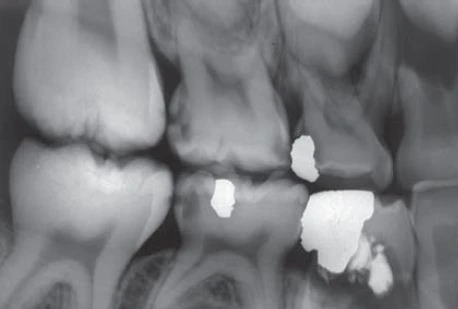

ĐA SÂU RĂNG

Sâu răng phá huỷ răng tiến triển nhanh và rầm rộ thường được gọi là đa sâu răng và thường thấy ở trẻ em có chế độ dinh dưỡng không đầy đủ và thói quen vệ sinh răng miệng kém. Tuy nhiên, tình trạng này ngày càng hiếm do việc bổ sung fluor trong nguồn nước, sử dụng fluor tại chỗ và nâng cao kiến thức về dinh dưỡng cũng như vệ sinh răng miệng. Đa sâu răng có thể thấy ở những người bị chứng khô miệng. X quang của những cá nhân này cho thấy hình ảnh sâu răng phá tuỷ trầm trọng, tiến triển, đặc biệt là những răng trước hàm dưới.

THỦ THUẬT SAU KHI XẠ TRỊ

Những bệnh nhân được điều trị xạ trị ở vùng đầu và cổ có thể mất chức năng tuyến nước bọt, dẫn đến khô miệng, thay đổi hệ khuẩn chí vùng miệng và có khả năng thay đổi nội tại cấu trúc răng. Nếu không điều trị, điều này có thể gây nên phá huỷ răng hàng loạt, còn gọi là đa sâu răng. Thông thường, sự phá huỷ bắt đầu tại vùng cổ răng và có thể tiến triển nhanh vòng quanh thân răng, dẫn đến mất toàn bộ thân răng và chỉ còn lại mảnh chân răng trên cung hàm. Hình ảnh X quang của sâu răng do xạ trị có những nét đặc trưng: bóng thấu quang nằm ở vùng cổ răng, hầu hết rõ nét ở mặt gần và mặt xa. Hiện diện những biến thể độ sâu của tổn thương phá huỷ, nhưng thường có sự thống nhất trong một vùng trong miệng. Hình bên dưới biểu thị một dẫn chứng của sâu răng ở bệnh nhân bị khô miệng sau khi thực hiện liệu pháp xạ trị ung thư vùng đầu và cổ. Sử dụng liệu pháp fluor tại chỗ như là dung dịch tái khoáng hoá và vệ sinh răng miệng kỹ càng có thể làm giảm đáng kể những tác hại của xạ trị lên răng do khô miệng.

Hình 19. Sâu răng sau xạ trị